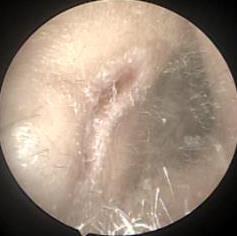

• 耳内镜下耳屏软骨-软骨膜鼓膜修补术后的短期疗效观察

摘要:目的 探讨耳内镜下耳屏软骨-软骨膜鼓膜修补术后的短期疗效。方法 回顾性分析2019年9月-2022年8月该院收治的78例鼓膜穿孔患者的临床资料,患者均采用耳内镜下鼓膜修补术。术后随访3个月,观察鼓膜形态和穿孔愈合情况,记录内镜图像、干耳时间、术前术后听力及耳鸣情况,以及外耳道狭窄等并发症的发生率。结果 术后3个月,鼓膜穿孔愈合率为97.44%(76/78),愈合良好,平均气导听阈较术前明显改善,气骨导间距较术前明显缩小,耳鸣较术前明显改善,差异均有统计学意义(P<0.05)。干耳时间为(4.21±1.12)周。术后出现肉芽5例,再穿孔2例,真菌感染2例,术腔感染、耳屏感染、外耳道狭窄和切口瘢痕各1例,所有患者术后均未发生面神经麻痹和感音神经性聋等严重并发症。结论 耳内镜下耳屏软骨-软骨膜鼓膜修补术是一种安全、有效的手术方法。根据术后愈合规律、内镜下鼓膜和外耳道形态特征,可为鼓膜修补术后正常中耳转归和并发症的诊疗,提供临床参考。